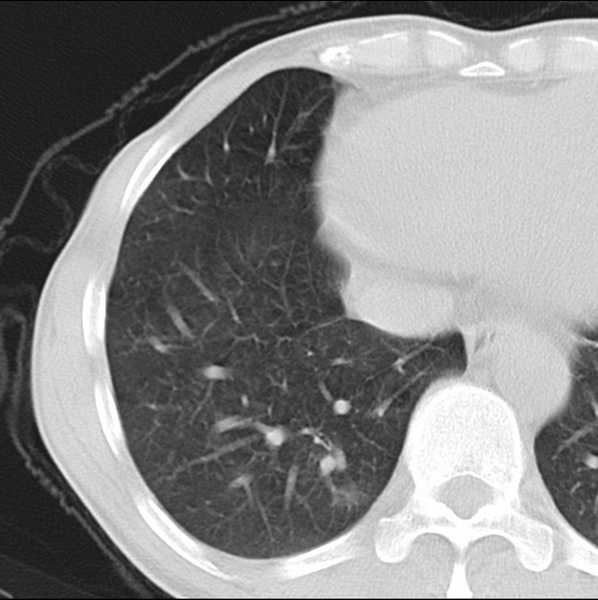

男、48、咳嗽。

胸片示双肺纹理紊乱,行胸部ct检查。

右肺下叶基底段结节影,双肺粟粒样阴影,ct值测量约-20hu左右,可能不准。

层厚层距为4mm左右,病灶轴面最大径约1cm左右。